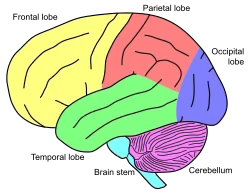

O cerebelo é uma região localizada na fossa posterior do crânio, e é coberto superiormente pelo tentório do cerebelo. É a maior parte do rombencéfalo e situa-se posteriormente ao quarto ventrículo, ponte e bulbo. O cerebelo tem um formato ligeiramente ovoide e apresenta uma constrição em sua parte mediana. É constituído por dois hemisférios do cerebelo, unidos pelo verme do cerebelo mediano e estreito. O cerebelo está conectado com a face posterior do tronco encefálico por três feixes simétricos de fibras nervosas, denominados pedúnculos cerebelares superior, médio e inferior.[1]

Anatomia

O cerebelo é a maior massa do encéfalo que se encontra dorsal à ponte e o bulbo, formando com essas estruturas a cavidade do quarto ventrículo. Situa-se abaixo do tentório do cerebelo na fossa posterior do crânio, separado do cérebro por um folheto da dura-máter. Possui formato praticamente ovalado, porém constringido mediamente e achatado na porção inferior, tendo seu maior diâmetro no sentido latero-lateral. Sua superfície não é convoluta como a do cérebro, porém cruzada por numerosos sulcos, que variam de profundidade dependendo da localização. Seu peso médio no homem é de aproximadamente 150 g. Em um adulto a proporção entre o cerebelo e o cérebro é de 1:8, em crianças é de 1:20. Consiste em dois hemisférios laterais unidos por uma parte média estreita, o vermis. Podemos dividi-lo em substância branca (interior) e substância cinzenta (exterior). A substância branca é constituída por fibras nervosas mielinizadas eferentes e aferentes. A substância cinzenta pode ser subdividida em 3 camadas: -Camada molecular -Camada de células de purkinje -Camada granular

O Cerebelo fica situado na fossa craniana posterior (fossas cerebelares do occipital), sendo coberto superiormente pela tenda do cerebelo. Constitui a maior parte do cérebro posterior, ficando posterior ao quarto ventrículo, à ponte e ao bulbo.